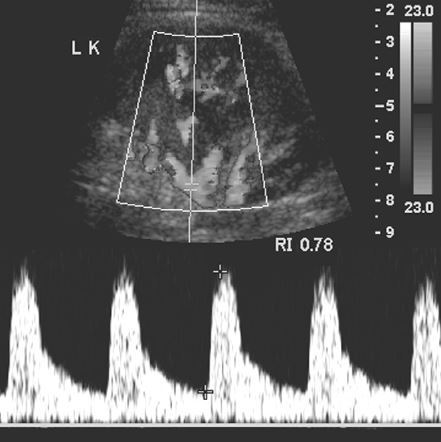

Renal artery stenosis

• 5% of total number of patients with HTN

• criteria

• PSV > 180-200cm/sec

• Renal/aortic ratio > 3.0-3.5